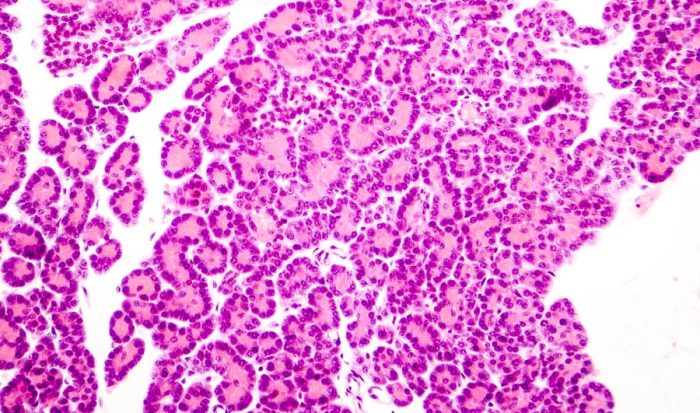

La diabetes mellitus tipo 1 es consecuencia de interacciones de factores genéticos, ambientales e inmunológicos, que culminan en la destrucción de las células beta del páncreas y la deficiencia de insulina.

La diabetes mellitus tipo 1 puede desarrollarse a cualquier edad, comienza con mayor frecuencia antes de los 20 años de edad. Dicha enfermedad es consecuencia de destrucción autoinmunitaria de las células beta del páncreas, y muchas personas que la tienen expresan manifestaciones de autoinmunidad dirigida contra islotes.

Los individuos con predisposición genética tienen una masa normal de células beta al momento del nacimiento, pero comienzan a perderla por destrucción inmunitaria a lo largo de meses o años. Se piensa que este proceso autoinmunitario es desencadenado por un estímulo infeccioso o ambiental, y que es mantenido por una molécula específica de las células beta. En la mayoría de los individuos aparecen inmunomarcadores después del suceso desencadenante pero antes de que la enfermedad se manifieste clínicamente. Después empieza a declinar la masa de las células beta y se trastorna en forma progresiva la secreción de insulina, a pesar de mantenerse una tolerancia normal a la glucosa.

La velocidad de declive de la masa de células beta pancreáticas es muy variable de un individuo a otro, y algunos pacientes avanzan rápidamente al cuadro clínico de diabetes, mientras en otros la evolución es más lenta. Las características de la diabetes no se hacen evidentes sino hasta que se ha destruido la mayor parte de las células beta, alrededor de 70 a 80% de la masa celular. En este punto, todavía existen células beta residuales, pero son insuficientes en número para mantener la tolerancia a la glucosa.